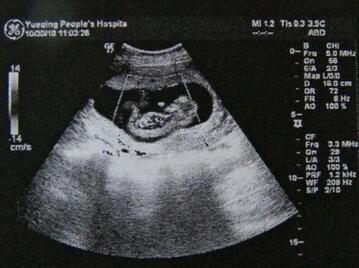

1、服药前做B超检查,确认是宫内孕。

[流产胎停]一般怀孕5-7周之间可以做药物流产,一定经过B超诊断是在宫内怀孕而且怀孕的天数不可以超过49天才适合药物流产。并且药物流产最好是初次怀孕,以往没有人工流产病史,或者是没有孕产史